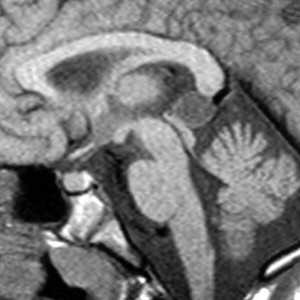

(Слева) На МР Т1ВИ в сагиттальной проекции в корне языка визуализируется врожденная киста валлекулы с ровными краями, содержимое которой имеет сигнал, характерный для жидкости.

(Справа) На МР Т2ВИ в корональной проекции у этого же пациента в передних отделах ротоглотки визуализируется валлекулярная киста с неровным контуром и сигналом, типичным для жидкости.